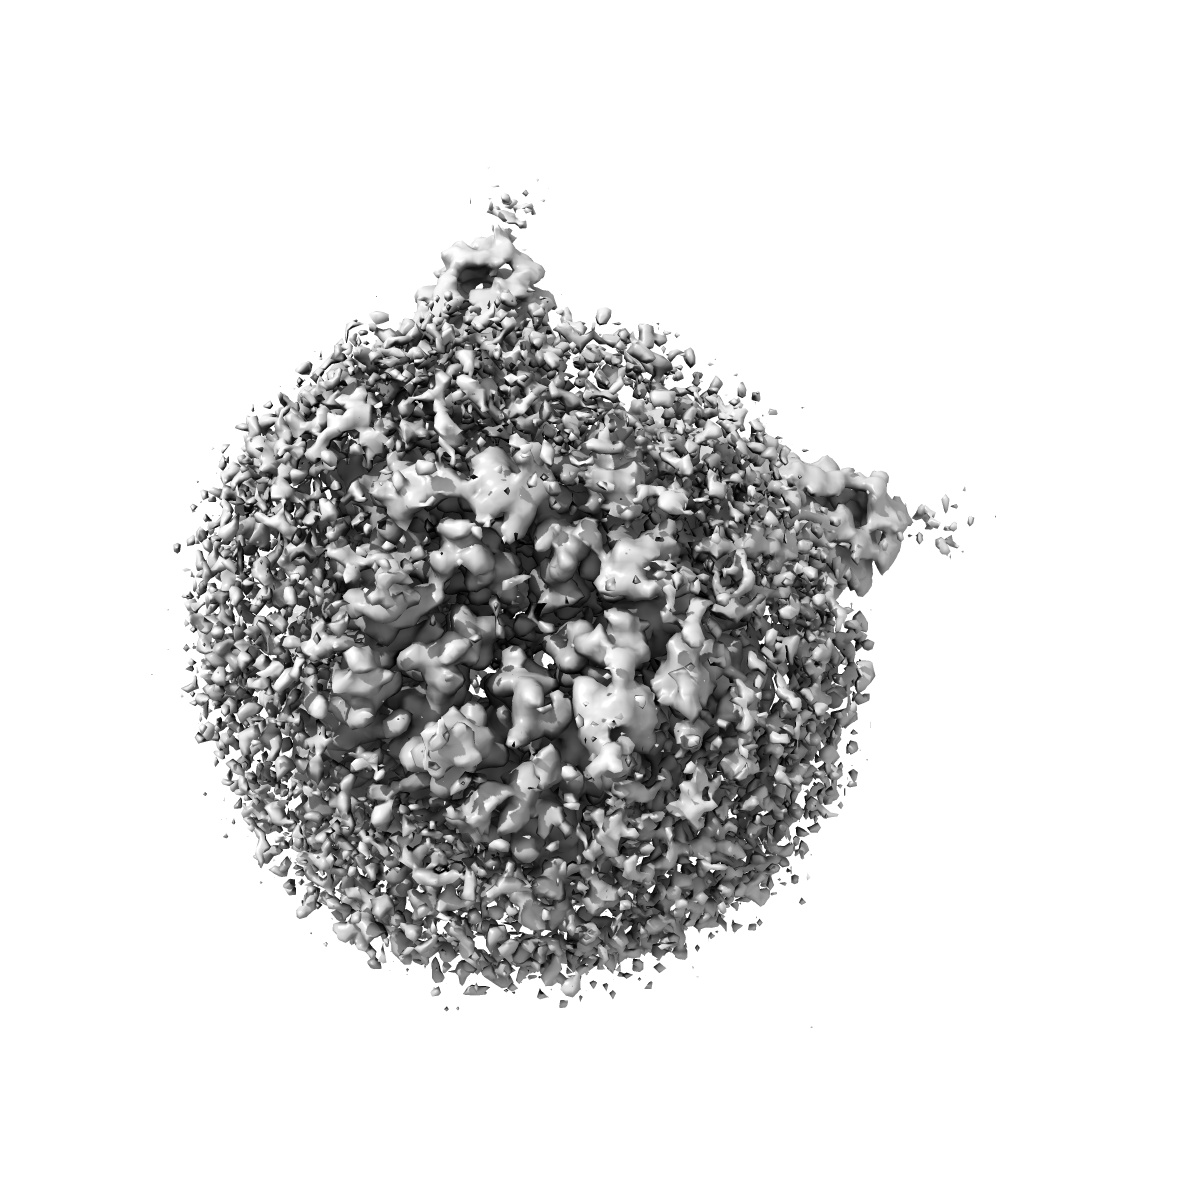

Cryo-EM structure of human full-length extrasynaptic alpha4beta3delta GABA(A)R in complex with nanobody Nb25

Single-particle2.5 Å

Sample: Human full-length extrasynaptic alpha4beta3delta GABA(A)R in complex with Nanobody Nb25